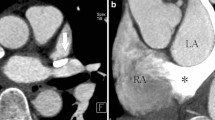

Imaging in a 4-day-old boy born with double-outlet right ventricle, subpulmonary ventricular septal defect and interrupted aortic arch. Axial oblique (a) and sagittal oblique (b) cardiac CT images demonstrate the single but separate coronary artery origins (a) and the proximal right coronary artery (b), which was confirmed at arterial switch operation. 1 sinus 1, 2 sinus 2, DA descending aorta, LA left atrium, LCA left coronary artery, PT pulmonary trunk, RA right atrium, RCA right coronary artery

Imaging in a 4-day-old boy born with transposition of the great arteries and intact ventricular septum. Axial oblique (a) and sagittal oblique (b) cardiac CT images demonstrate the single coronary artery origins (a) and the proximal coronary arteries (b), which was confirmed at arterial switch operation. Almost complete anteroposterior relationship of the great arteries and severe commissural malalignment are noted (a). Patent ductus arteriosus (asterisks) is also seen (b). 1 sinus 1, 2 sinus 2, DA descending aorta, LA left atrium, LCA left coronary artery, PT pulmonary trunk, RA right atrium, RCA right coronary artery, S single coronary artery